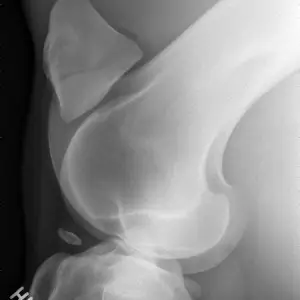

Die Anwendungsbereiche für röntgenologische Untersuchungen sind sehr vielfältig. Fast jede Lahmheitsuntersuchung und orthopädische Untersuchung erfordert die röntgenologische Darstellung bestimmter Gliedmassenabschnitte in mehreren Ebenen. Nahezu jede Kaufuntersuchung beinhaltet neben der klinischen Untersuchung auch die Erstellung von Röntgenbildern der Gliedmaßen und in vielen Fällen auch der Oberlinie. Bei bestehenden Rittigkeitsbeschwerden wird häufig eine Röntgenuntersuchung des Halses und des Rückens vorgenommen. Aufgrund der Leistungsstärke unserer Röntgenanlagen ist es uns häufig möglich, auch den Beckenbereich des Pferdes inklusive Hüftgelenk am stehenden Pferd zu untersuchen.